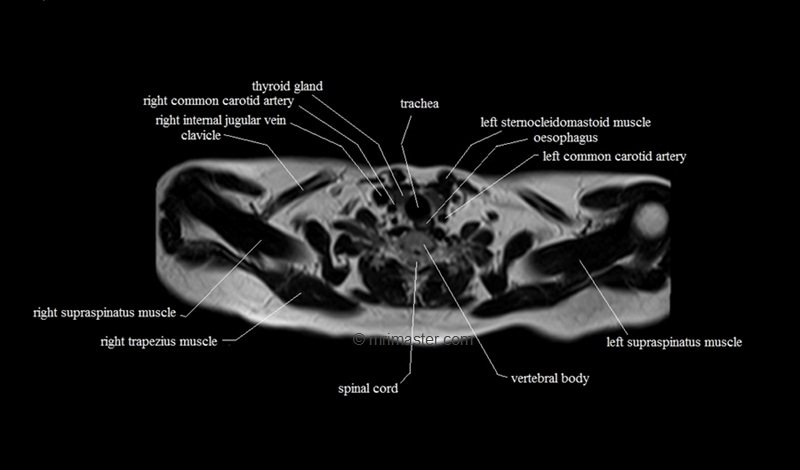

MRI Axial Cross Sectional Anatomy of Chest

This MRI chest (thorax) axial cross sectional anatomy tool is absolutely free to use. Use the mouse scroll wheel to move the images up and down, or alternatively, use the tiny arrows (→) on both sides of the image to navigate through the images. For a more detailed view, double-click the image to view it in full screen, and use the menu in the top right-hand corner to view individual slides or play them in a loop.